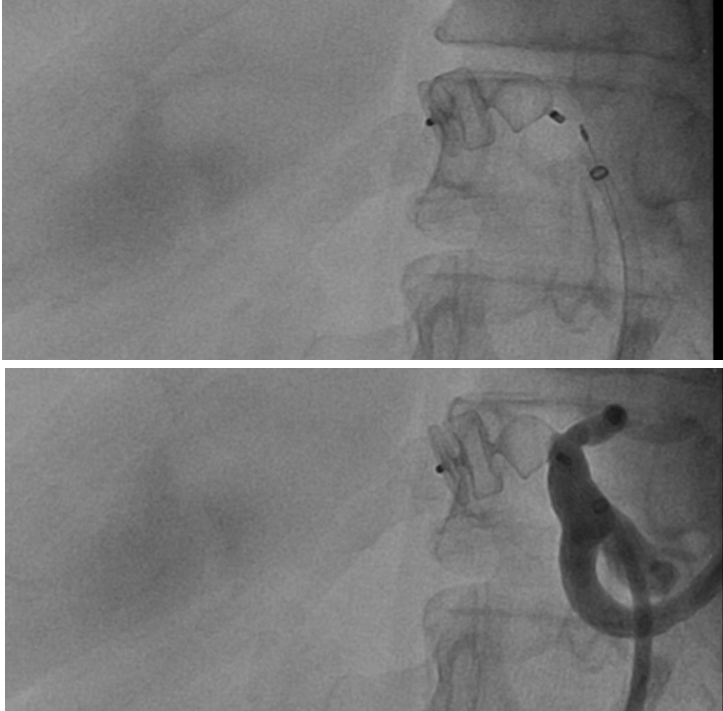

- Angiografia: Um exame invasivo que permite visualizar a artéria hepática e o aneurisma com o uso de contraste radiopaco. Permite evidenciar o tamanho, a forma e a localização do aneurisma, permitindo uma programação terapêutica, além de delimitar a eventual presença de circulação colateral.

A abordagem endovascular vem ganhando espaço no tratamento dos AAH, especialmente em procedimentos eletivos, devido à alta taxa morbimortalidade na cirurgia aberta. A principal vantagem é a menor invasividade, especialmente útil para pacientes de alto risco. Sendo assim, essa abordagem é inicialmente recomendada para todos os AAH que sejam anatomicamente viáveis, ou seja, quando é possível manter a circulação arterial para o fígado. As abordagens intervencionistas no AAH podem ser realizadas através de implante percutâneo de endopróteses para exclusão endovascular do aneurisma, através da oclusão da artéria hepática (por embolização) ou através do reparo cirúrgico aberto da dilatação arterial (ressecção cirúrgica com interposição de enxerto). Em relação às técnicas endovasculares, uma vez que a manutenção da perfusão do órgão distal é importante, o stent recoberto é sempre preferível à embolização em espiral. Os procedimentos reconstrutivos são indicados, principalmente, quando uma vascularização colateral para o segmento hepático relacionado não estiver presente.